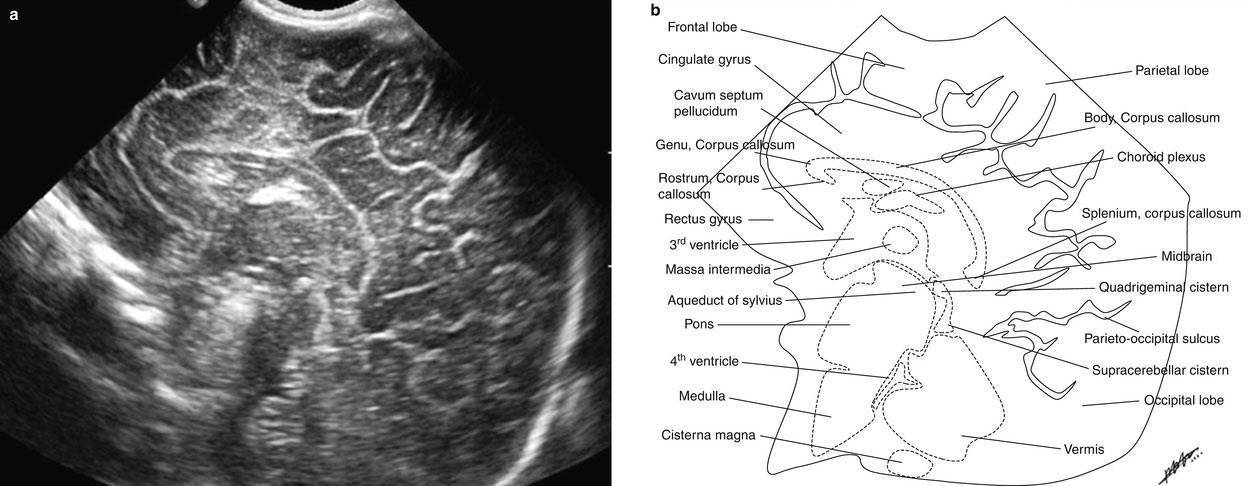

Рисунки: снимки и расположение структур мозга

Борозды и извилины коры мозга отражают степень его зрелости. Извилины полушарий активно дифференцируются с 28 недели беременности и становятся видны при УЗИ спустя 2-6 недель после того, как сформируются в анатомические структуры. После рождения ребенка локализация и количество борозд и извилин в норме соответствуют строению мозга взрослого человека.

Желудочковая система представлена четырьмя сообщающимися полостями, заполненными спинномозговой жидкостью. Боковые желудочки по мере увеличения срока беременности суживаются, становясь щелевидными, каковыми и остаются в норме и у ребенка, и у взрослого. Допускается некоторая асимметрия желудочков в пределах двух миллиметров на уровне отверстия Монро, которая считается вариантом нормы.

Из всех отделов мозга наиболее удален от большого родничка мозжечок, поэтому он хуже всего просматривается при нейросонографии. В норме он должен иметь два сформированных полушария и червь, расположенный между ними. Поперечник мозжечка пропорционален диаметру головы плода, поэтому этот показатель может служить для определения срока беременности.